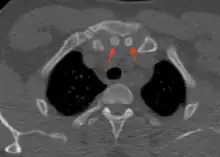

Axial computed tomography showing the episternal ossicles (red arrows)

The episternal ossicles are oval-shaped bones that are occasionally found at the superior and posterior border of the manubrium. The episternal ossicles were first described by Cobb in 1937.[2] They may be present unilaterally or bilaterally.[3] Its size ranges from 2–15 mm depending on individuals.[4] These ossicles are asymptomatic and does not cause any harm, although it may be diagnosed as fracture, vascular ossification or calcified lymph nodes.